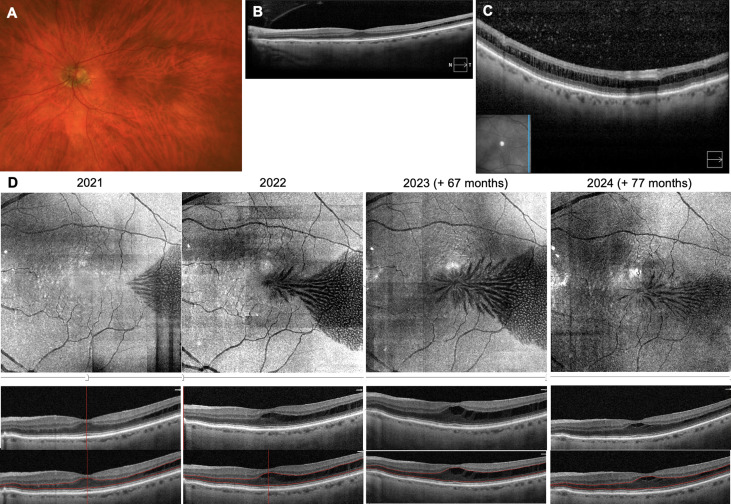

Stellate Nonhereditary Idiopathic Foveomacular Retinoschisis and Central Anomalous Retinoschisis with mid-PEripheral Traction (CARPET) ow.ly/B5a150UZmaX #ophthalmology #retina

Stellate Nonhereditary Idiopathic Foveomacular Retinoschisis and Central Anomalous Retinoschisis with mid-PEripheral Traction (CARPET)

ow.ly/B5a150UZmaX

#ophthalmology #retina